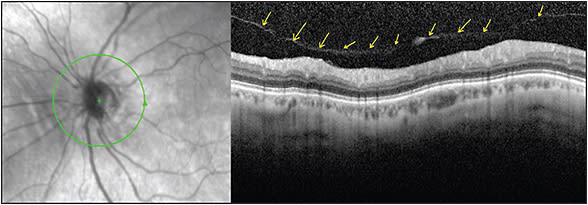

One of the very commonly used modules of OCT can be very useful in unequivocally and very reliably (approximately 95% specificity and sensitivity, based on the author’s experience) demonstrating a PVD. The nerve fiber layer (NFL) module of the OCT (Heidelberg or Zeiss) often demonstrates a line above the retina. This, in the author’s opinion, represents posterior hyaloid still attached to the ONH (Figures 1 and 2). Note the faint nature of the reflection in Figure 1A. Most of the time, however, the line is much more defined and much more easily visualized, as in Figure 1B. This easy use of an already existing module on all OCT machines has proven to be very reliable and has helped us advise patients more accurately, especially when a Weiss ring is not visualized.